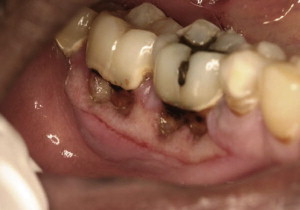

What kind of post-developmental loss of tooth structure is this?

Attrition *caused by bruxism*